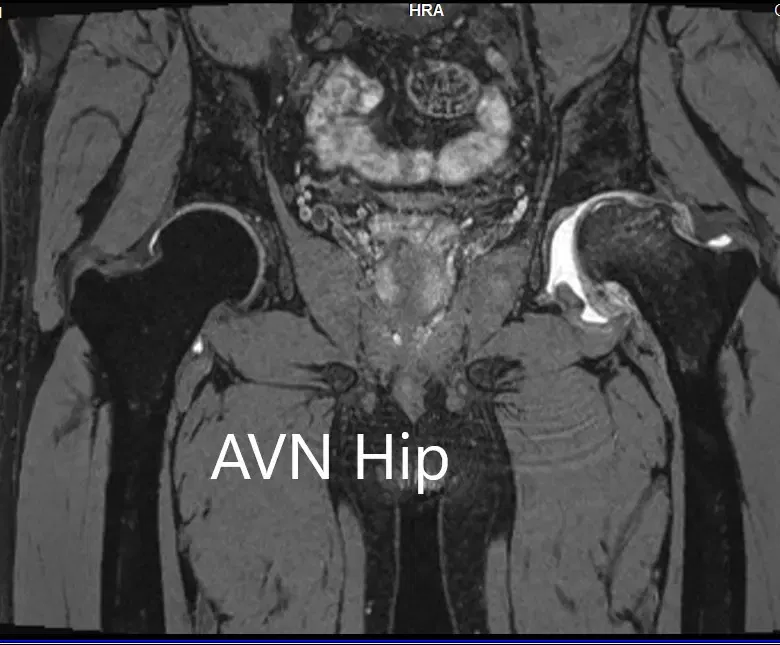

Se realizó una resonancia magnética para confirmar el diagnóstico y la estadificación de la enfermedad. La cabeza femoral izquierda estaba colapsada con contorno irregular y mostraba áreas de intensidad de señal alterada con una línea de demarcación. Zonas hipointensas tanto en T1WI como T2WI observadas en la cabeza sugestivas de esclerosis. Se observó edema de médula circundante

La cadera izquierda presentaba necrosis avascular avanzada con colapso. La cadera derecha no estaba afectada en ese momento. Recibió formación sobre el agravamiento del colapso de la articulación de la cadera que provocaba sus síntomas. Aunque el paciente era joven, se le recomendó una cirugía de reemplazo total de cadera debido al colapso de la cabeza del fémur por artritis.